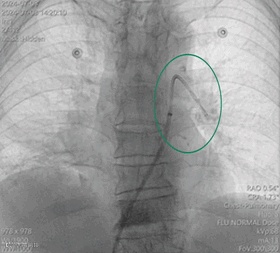

手术过程